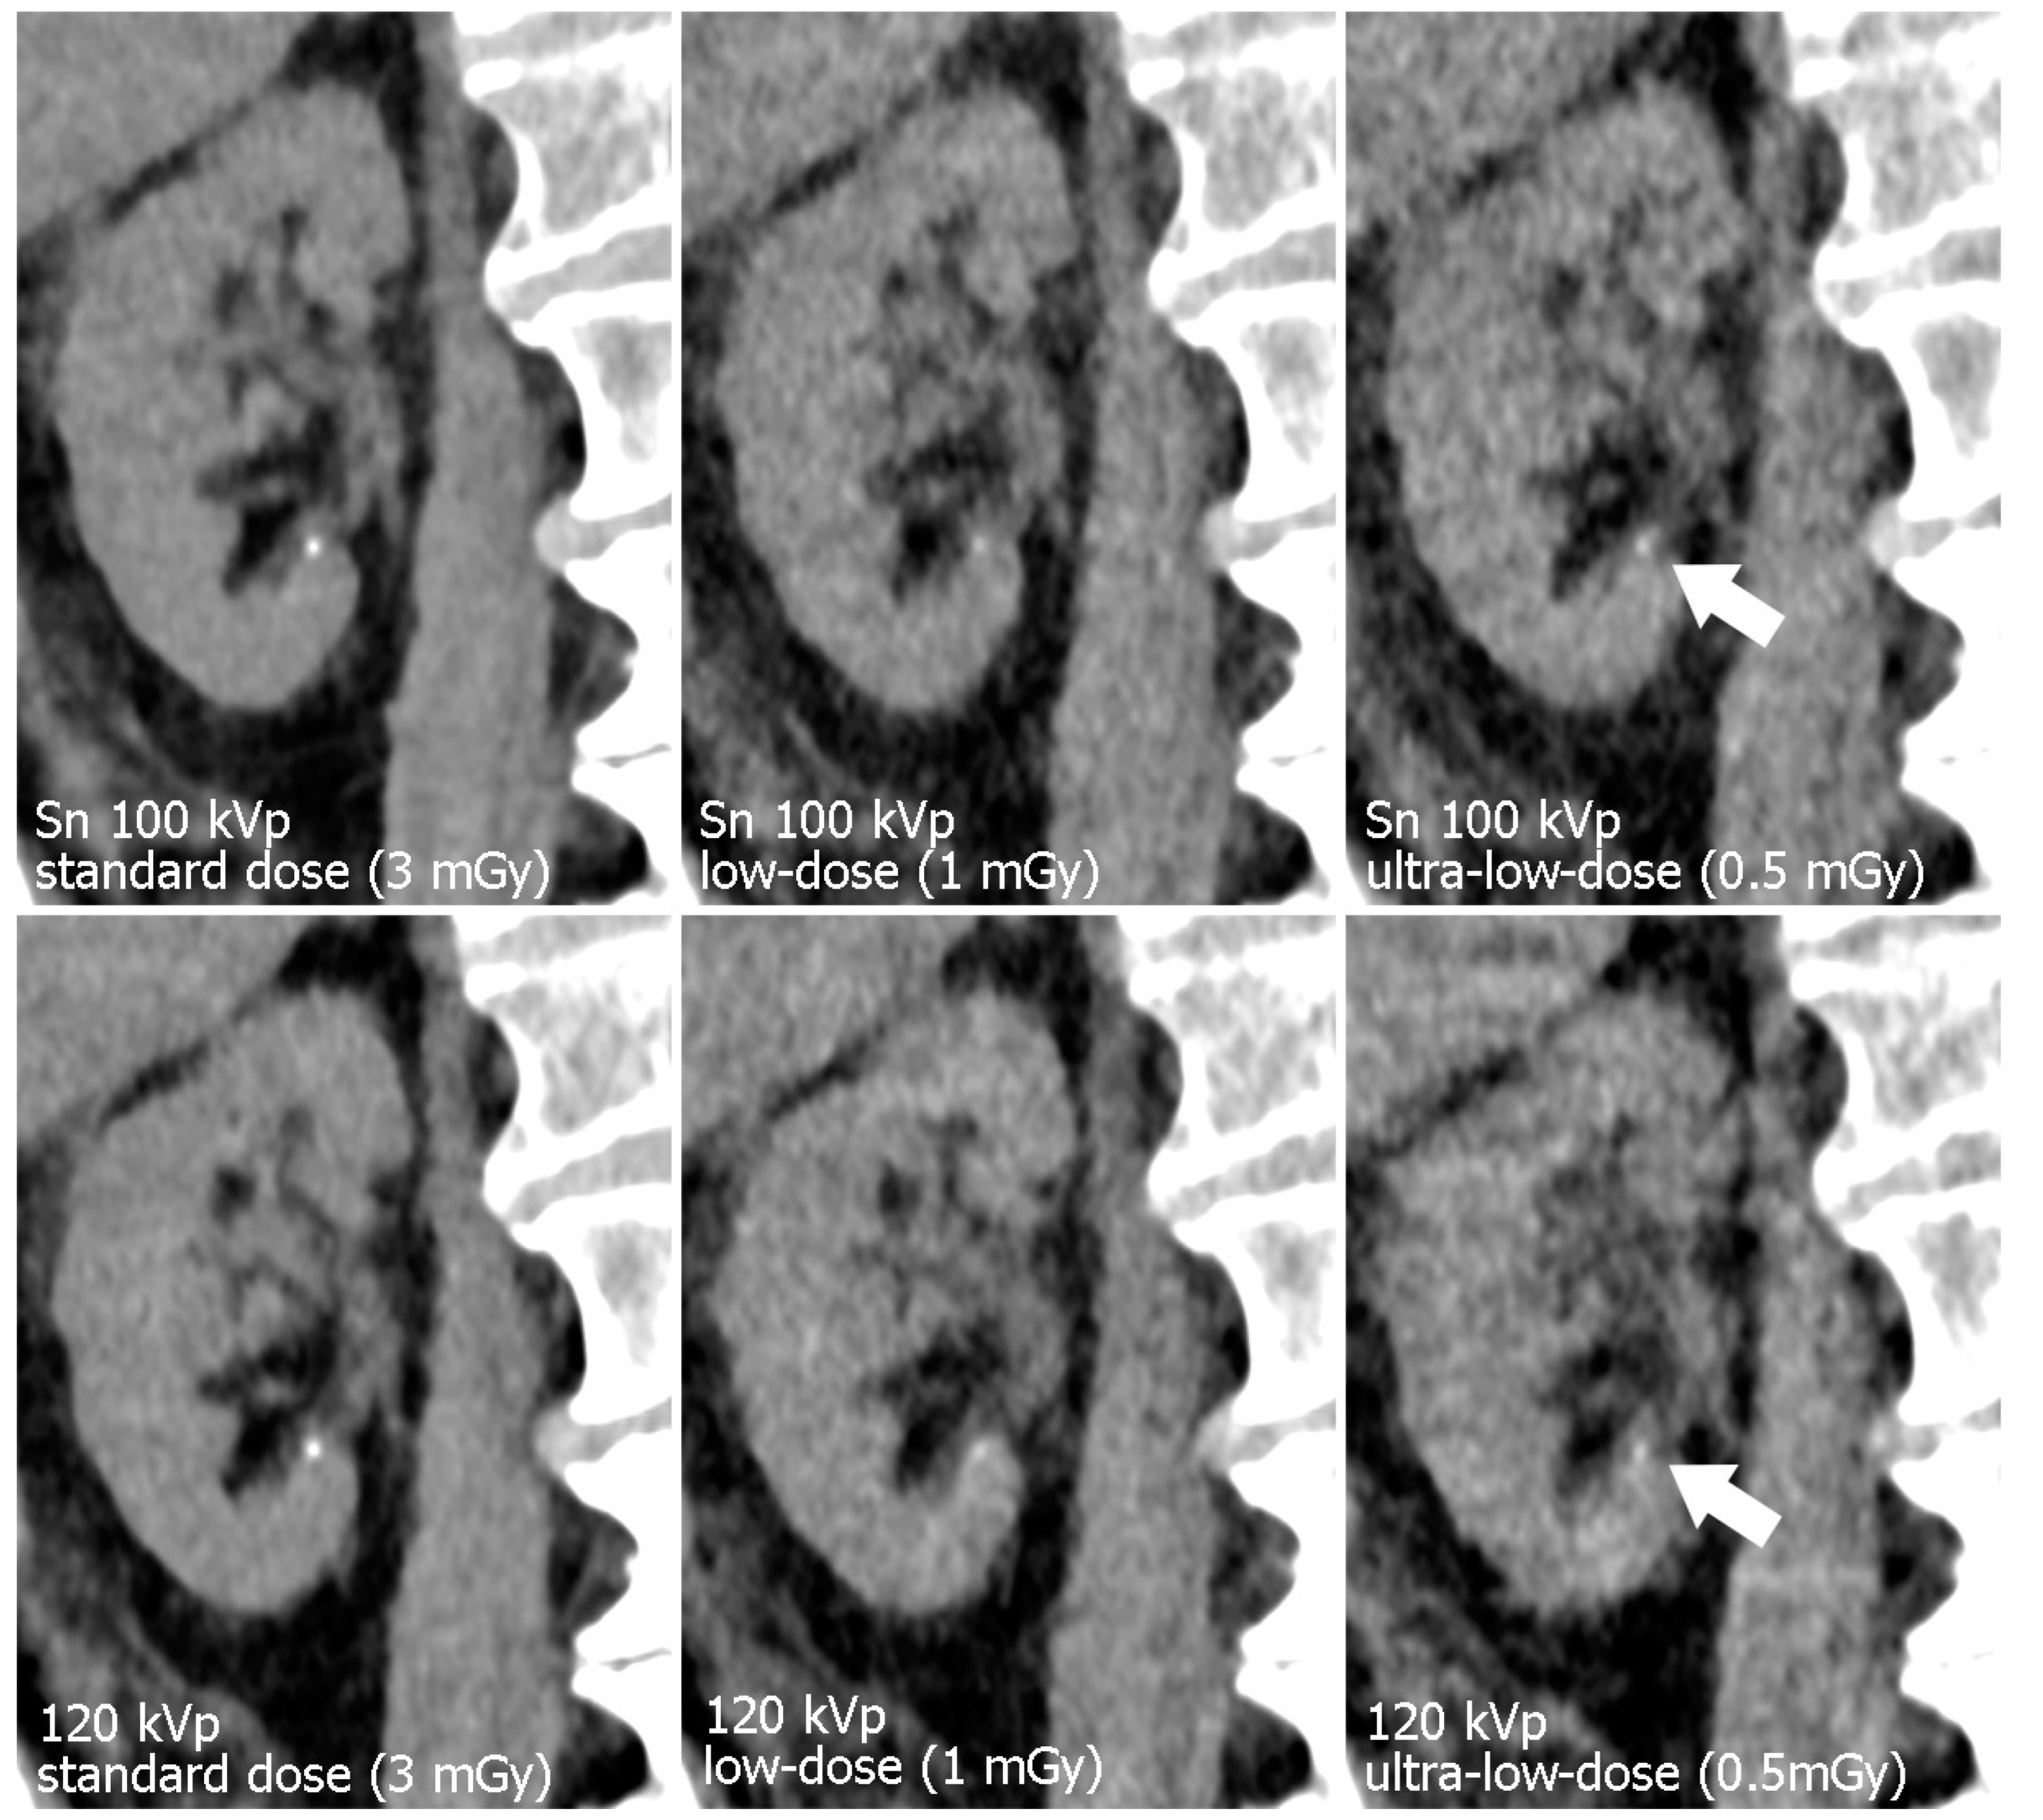

Figure 3.

Para-coronal images displaying the left kidney. The renal pelvis is not dilated but pelvic structures remain assessable even in ultra-low-dose images. Note the increased noise in the 120 kVp ultra-low-dose study compared to the dose-matched protocol with tin filtration.

Figure 4.

Para-coronal images of the right kidney display a minuscule calcification (arrow). Note the decrease in image quality with lower radiation dose. Organ margins and the calcification appear sharper with tin filtration ultra-low-dose imaging.